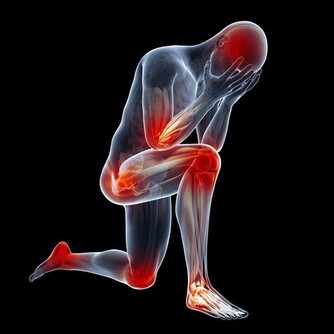

頸椎病會給大家帶來哪些危害 1、吞咽困難:感覺食管內有異物,吞咽困難,少數人有噁心、嘔吐、乾咳等症狀。這是由於頸椎骨質增生壓迫食管後壁,引起食管狹窄所致。 2、視覺障礙:頸椎病多會影響到人們的頭部,頸椎病會造成自主神經紊亂及血液供應不足導致大腦視覺中樞缺鐵性病變有關。主要表現為視力下降、眼睛酸痛、怕光、流淚等症狀,個別的患者會出現失明的嚴重後果。 3、猝倒:由於頸椎病多會影響人們出現不適症狀,常常會出現頭暈、噁心頭昏眼花等症狀。猛然發作,容易造成猝倒,危機生命安全。 4、下肢癱瘓:患者的病情若是長期沒能控制,會出現很多其他症狀,早期表現為下肢麻木、行走顛簸、疼痛,隨著病情的發展會出現陰部麻木,導致大小便失禁,更嚴重的會出現下肢癱瘓,失去自理能力。 大家在選擇治療方法時,應根據自身的具體病情選擇,若病情尚輕可採取保守治療,若病情已經非常嚴重,建議採用微創治療。微創治療是骨科臨床的一種新型治療方式,此技術創傷小,基本不留疤痕,是無創傷的治療技術,而且此技術對於對身體組織沒有傷害,患者疼痛小,術後恢復時間短,住院時間短,可輕鬆的讓患者擺脫病痛的折磨。 微創顯微鏡技術治療頸椎病,只要在患者頸部開幾個直徑不到1公分的小孔,藉助顯微鏡,將神經、血管放大10倍以上,在這樣的環境下手術,不僅可以儘可能減少傷害到患者的神經組織,同時又避免了神經組織受傷後的連鎖反應,如傷口的合併感染、其他併發症等。這種技術手術切口更小,視野更清晰,手術更精確,更安全,是頸椎病患者值得選擇的治療方式。 相關標籤: 健康 養生 頸椎病 收藏 分享 投訴